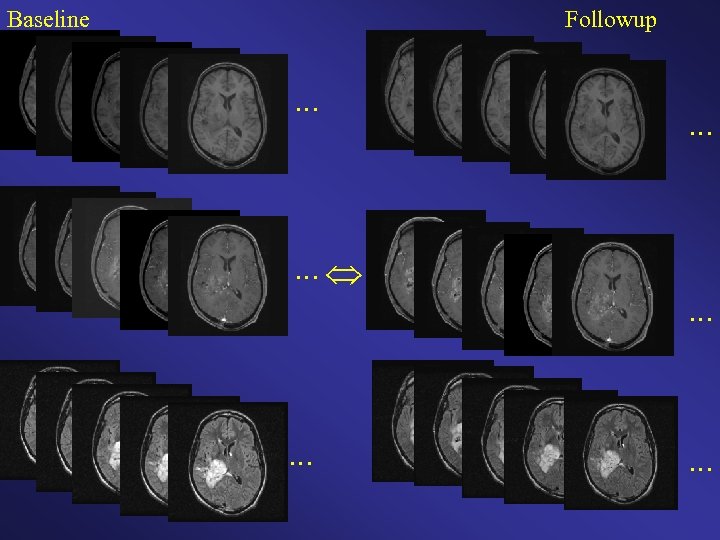

Baseline Followup